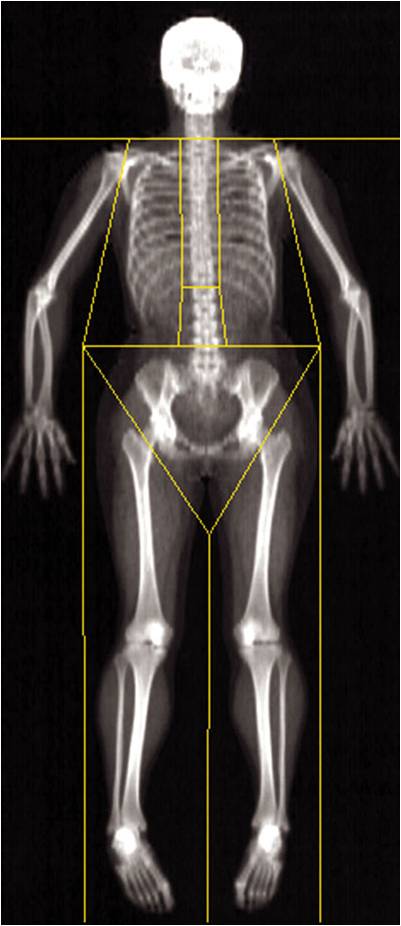

(五)DEXA法